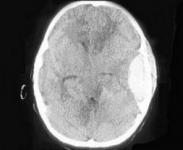

• 硬腦膜外膿腫

628健康網為您分享有關硬腦膜外膿腫的癥狀,硬腦膜外膿腫的治療方法,硬腦膜外膿腫的預防知識,硬腦膜外膿腫的癥狀圖片,硬...